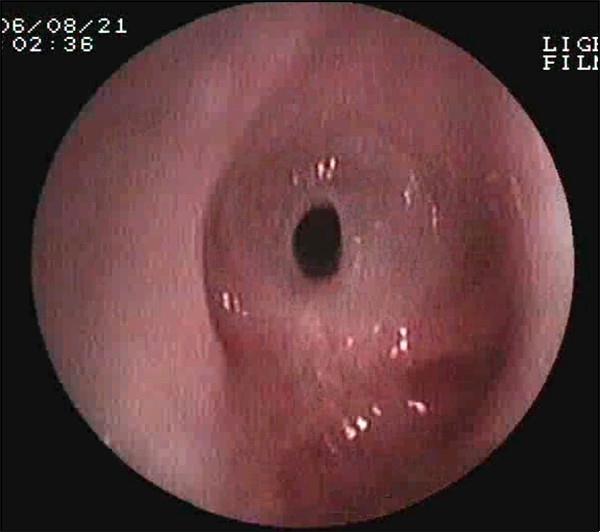

气道狭窄